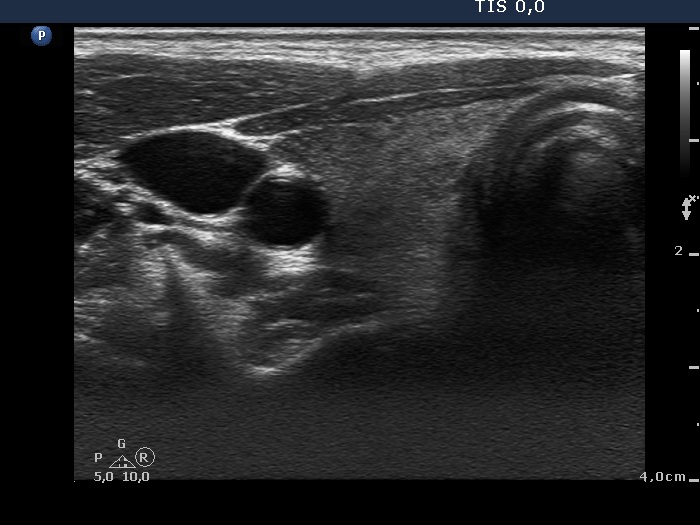

First examination (1st and 4th rows of images):

Clinical presentation: A 34-year-old woman was referred for an evaluation of neck complaints. Neck pain and fever started 2 month ago and lasted for 3 weeks. Then complaints suggesting hyperthyroidism have developed. The neck complaints have decreased. The body temperature has normalized.

Palpation: The right lobe was tender and hard on palpation.

Functional state: hyperthyroidism with TSH 0.01 mIU/L and FT4 27.2 pM/L, CRP 12.8 mg/L (normal value 0-4.8), TSAb 0 U/L.

Ultrasonography: The thyroid was echonormal and presented hypoechogenic areas with ill-defined borders. The vascularization was average.

Aspiration cytology was performed from right thyroid and resulted in subacute, granulomatous, de Quervain's thyroiditis.